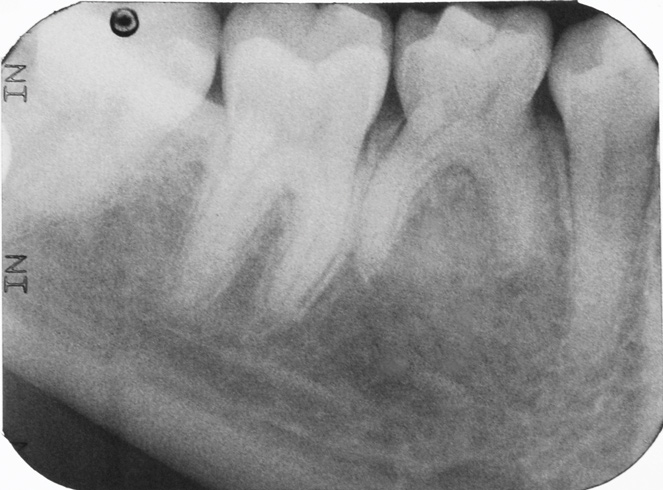

Fig 16. A 15-year-old girl with retained mandibular primary second molar and congenital absence of second premolar (Fig 16). In bitewing film small radiolucencies revealed beginning caries lesions at contact points of primary second molar and adjacent first molar (Fig 17); 12 months later, after initial SDF and 6-month follow-up SDF applications (Fig 18), radiolucencies were not evident.

Figure 16

Fig 17. A 15-year-old girl with retained mandibular primary second molar and congenital absence of second premolar (Fig 16). In bitewing film small radiolucencies revealed beginning caries lesions at contact points of primary second molar and adjacent first molar (Fig 17); 12 months later, after initial SDF and 6-month follow-up SDF applications (Fig 18), radiolucencies were not evident.

Figure 17

Fig 18. A 15-year-old girl with retained mandibular primary second molar and congenital absence of second premolar (Fig 16). In bitewing film small radiolucencies revealed beginning caries lesions at contact points of primary second molar and adjacent first molar (Fig 17); 12 months later, after initial SDF and 6-month follow-up SDF applications (Fig 18), radiolucencies were not evident.

Figure 18